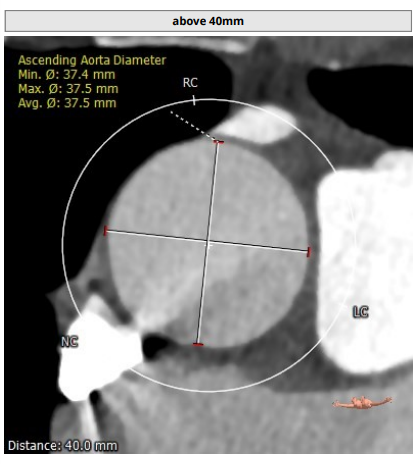

术前CT评估报告:

瓣环平均直径:26.3 mm,左室流出道平均直径:27.3 mm

主动脉窦部: 28.7 mm, STJ : 30.5 mm

左冠高度7.1mm, 右冠高度13.2mm.

升主动脉未见明显扩张,右侧股动脉符合入路条件